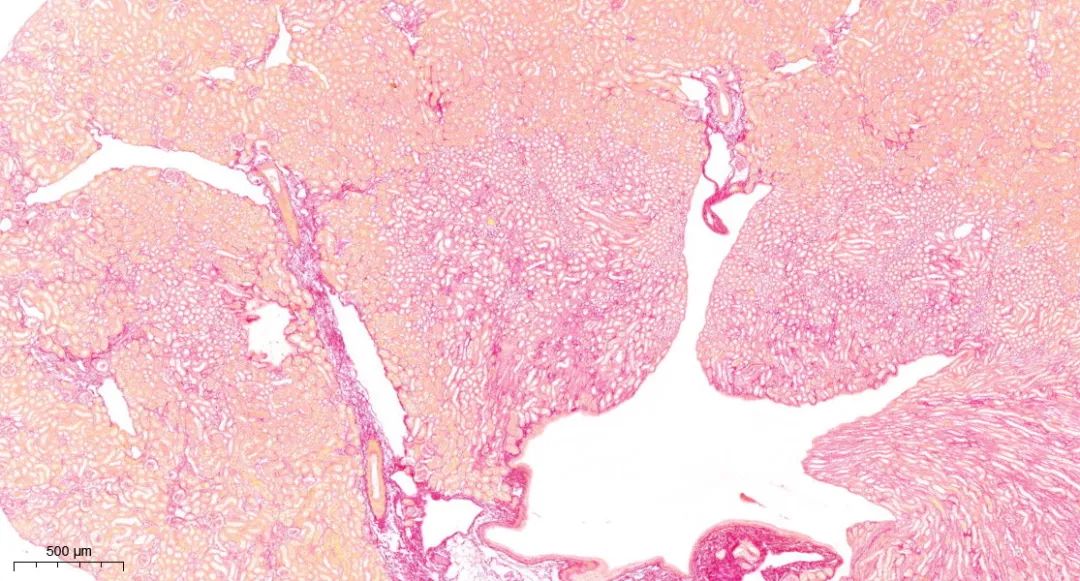

天狼星红染色

天狼星红染色主要用于定量分析胶原含量。

天狼星红与胶原形成复合物后,该复合物可在酸性环境中显示红色。更重要的是,天狼星红染色后的组织在偏振光下能显示出明显的双折射色,通过这种色彩变化,可以进一步区分不同类型的胶原(如I型和III型胶原)。

天狼星红染色实例